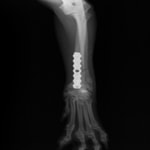

トイプードル 右遠位橈尺骨短斜骨折のALPSによる内固定

Locking Compression Plate

LCPは、スクリュー(ネジ)とプレート(金属の板)をロックする特殊な構造により骨折部位を固定する新しい世代のプレートシステムです。ひとつのホールでロッキングスクリューとスタンダードスクリューの使用を選択できるユニークな構造をしているため、骨折断端間の圧迫を目的とした従来型プレート固定法に加え、高い角度安定性を有するロッキングスクリューを用いた固定法の選択が可能です。従来のプレートシステムでは困難だった部分の骨折や癒合不全の症例に高い治療効果をもたらします。